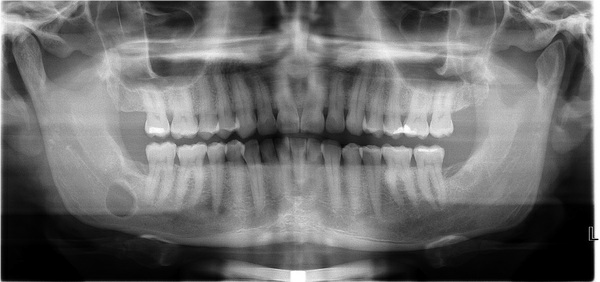

3. (Select ONE OR MORE correct answers)

The radiograph shows evidence of